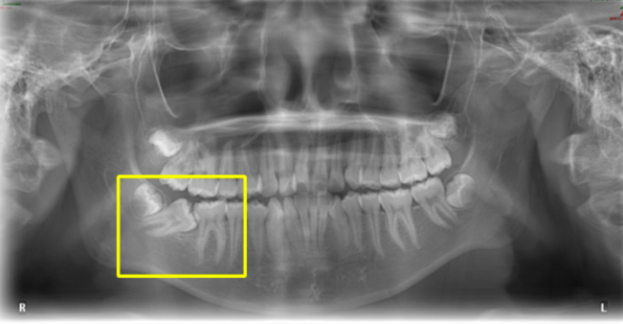

王嘉怡作为一名“大七”的八年制学生,进入口腔医学的临床工作,正式面对病人已经有两年多了。刚上临床时,王嘉怡曾接诊过一名14岁的女孩,右下第二磨牙在口内看不到完整的牙冠,只能在第一磨牙的后面看到勉强露出的一个牙尖。这颗牙经常会塞东西,牙龈出血,也难以咀嚼。王嘉怡一下子就犯了愁,这样“躺平”的牙还能扶起来吗?是不是只能拔掉了?可是女孩还年轻,少了这颗牙,咀嚼功能势必会受影响,而想要种牙还需要等到18岁以后。她在内心暗暗下了决心,至少要试着治好这颗牙。

带着疑问,王嘉怡上网查阅了中外文献,发现原来磨牙阻生并不少见,发病率约有1%。可以依靠位于下颌升支前缘的种植支抗钉将磨牙扶正。有了种植钉技术在手,她有了为小女孩治疗的信心。然而小女孩才14岁,这种治疗手段是否合适她?王嘉怡再次犯了难。

王嘉怡找到了导师李巍然教授,并提出了自己的疑问。李教授仔细研读了病历资料,提出这种治疗方案是一个有创的过程,可能会造成磨嘴不适的问题,而种植体植入难度也较大。

李教授给出了另一种治疗方案,女孩的阻生磨牙牙面露出面积较大,阻生角度并不过于水平,可以利用悬臂梁的原理,通过一枚形似弹簧的弓丝,推着磨牙立正。这种治疗方案不仅可以快速地扶正磨牙,更不需要有创操作,异物感也会小很多。

王嘉怡惊叹于正畸治疗中这些巧妙的技巧与手段,也懊恼于没能想到更适合患者的治疗方案。老师安慰地拍了拍她,说:“作为一名口腔大夫,我们要在临床上不断地摸爬滚打,积累经验。见得多了,武器库才能足够庞大,才能让我们面对每一名患者时都做到游刃有余,把病看好。”有了老师的指导,小女孩顺利开展了正畸治疗,磨牙也在逐渐扶正。